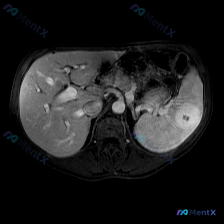

看到一个很有警示意义的影像病例,整理一下思路和大家分享: 最初的影像描述 这是一张腹部MRI轴位T2加权图像,可见一个边界清晰、形态规则的类圆形极高信号病灶,信号强度接近脑脊液(典型的“灯泡征”样表现),内部信号均匀,无明显分隔、结节或壁增厚,也未见对周围组织造成明显压迫或占位效应。 第一个容易踩的...

整理了一份脾脏占位的读片+分析思路,感觉这个病例的「混杂信号」挺有代表性,容易被带偏,分享出来一起理一理。 --- 一、先看影像核心表现 这份是上腹部MRI轴位T2加权像: - 肝脏、胃壁、腹膜后大血管这些都还好,没见明显异常; - 脾脏形态正常,但里面有一个类圆形占位,边界尚清; - 关键信号:T...